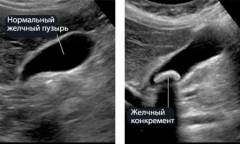

Желчный пузырь

Желчный пузырь расположен на нижней стороне печени, в углублении под её левой долей. Он проецируется на передней стенке живота на уровне пересечения правого края прямой мышцы с реберной дугой, в верхней правой части брюшной полости. Этот орган не является жизненно необходимым; он накапливает желчь, вырабатываемую печенью, и выделяет её по мере необходимости. После удаления желчного пузыря желчь поступает непосредственно из печени в двенадцатиперстную кишку, что может негативно сказаться на пищеварении.

Желчный проток обходит двенадцатиперстную кишку сзади и направляется к головке поджелудочной железы, соединяясь с её выводящим протоком и проникая в стенку кишки. На уровне желчевыводящего протока часто наблюдается застревание камней.

Боль в области желчного пузыря обычно возникает из-за спастических сокращений гладкой мускулатуры его стенок. Слизистая оболочка, выстилающая внутреннюю поверхность пузыря, обладает высокой чувствительностью. Острые края камней могут её повреждать, вызывая боль. Хроническое воспаление в этой области может привести к раковому перерождению клеток.

Холецистит — воспаление желчного пузыря, чаще всего вызванное образованием камней. Причины образования камней до конца не установлены, но они могут состоять из солей билирубина, холестерина и кальция.

Боль при желчнокаменной болезни возникает из-за повреждения слизистой оболочки желчного пузыря и спазмов гладкой мускулатуры. Приступ боли называется желчной коликой и может быть очень интенсивным. Эпицентр боли располагается в верхней части живота между правым подреберьем и эпигастрием и может длиться от 15 минут до нескольких часов.

Холецистит — это воспаление желчного пузыря, чаще всего вызванное образованием камней, известным как холелитиаз. Причины формирования камней до конца не изучены, но они обычно состоят из солей билирубина, холестерина и кальция, варьируясь по размеру от миллиметров до сантиметров.

Боль при желчнокаменной болезни возникает из-за повреждения слизистой оболочки желчного пузыря и спазмов его стенок. Приступ боли, называемый желчной коликой, может быть очень интенсивным и локализуется в верхней части живота, между правым подреберьем и эпигастрием. Он длится от 15-20 минут до 4-5 часов.